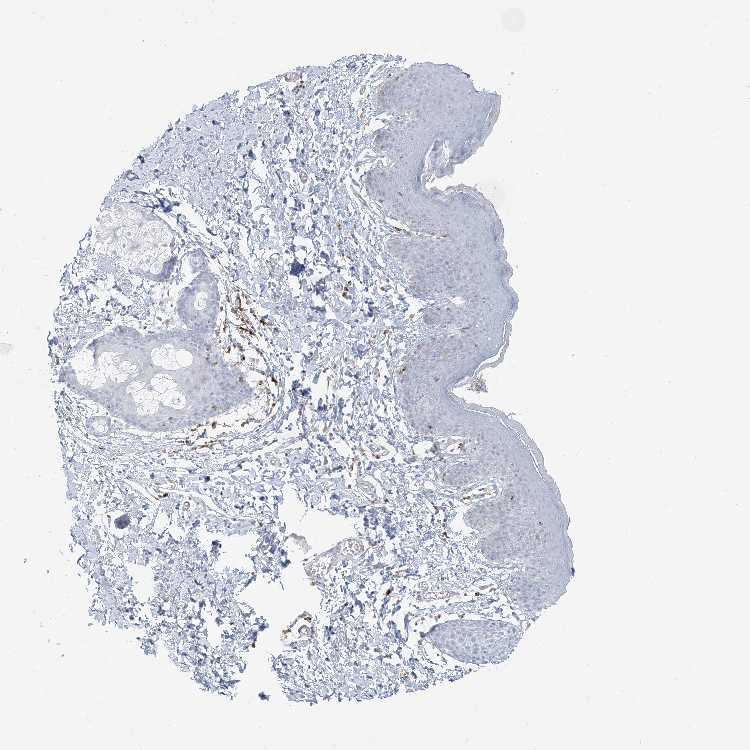

SKIN 2 - Antibody stainingi

Antibody staining in the annotated cell types in the current human tissue is reported as not detected, low, medium, or high, based on conventional immunohistochemistry profiling in selected tissues. This score is based on the combination of the staining intensity and fraction of stained cells.

Each image is clickable and will lead to virtual microscopy that enables deeper exploration of all samples and also displays staining intensity scores, fraction scores and subcellular localization as well as patient and tissue information for each sample.

Antibody HPA043151Antibody CAB015400Antibody CAB034021

Epidermal cells Not detectedNot detectedNot detected